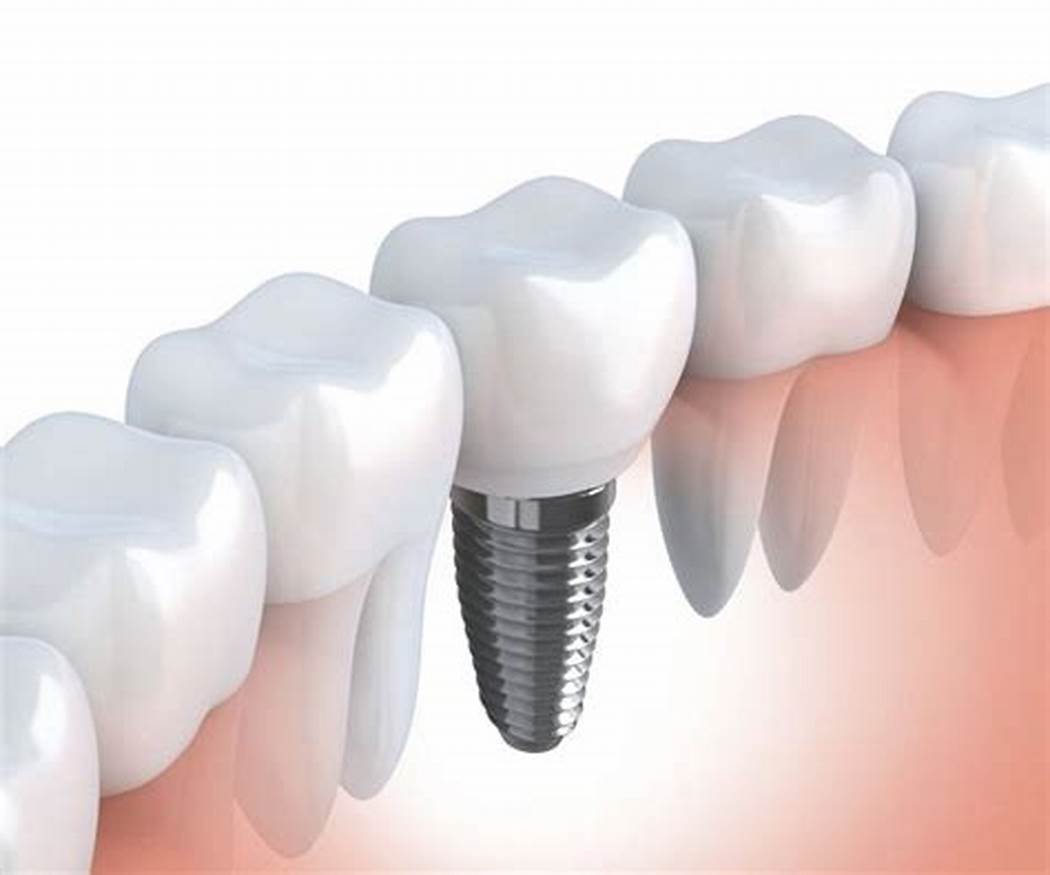

Implant Procedure:

When you choose Hope Health for dental implants, we offer you a distinctive treatment journey that guarantees the best results. We start with thorough and comprehensive examinations to determine the condition of your mouth and teeth, helping us create a tailored treatment plan to suit your needs. We use the latest technologies and advanced materials in implant procedures to ensure quick and effective treatment. Our medical team closely monitors your condition at every step, providing you with the necessary guidance to maintain the health of your implanted teeth for the long term. We strive to give you a bright and attractive smile that boosts your confidence and meets your satisfaction. With Hope Health, you’ll notice the difference from the first visit.

The procedure is performed under local anesthesia, which minimizes pain during the operation. Patients may experience some pain and swelling afterward, but this is usually temporary and can be managed with pain relievers.

The success rate of dental implants ranges from 95% to 98%, provided the patient follows the dentist’s care instructions for the implanted teeth.

Most people can undergo dental implant surgery, but a comprehensive evaluation of the mouth and jawbone is necessary. Some cases may require additional procedures, such as bone grafting before the implantation. Certain conditions, like osteoporosis and diabetes, may affect the success of dental implants.